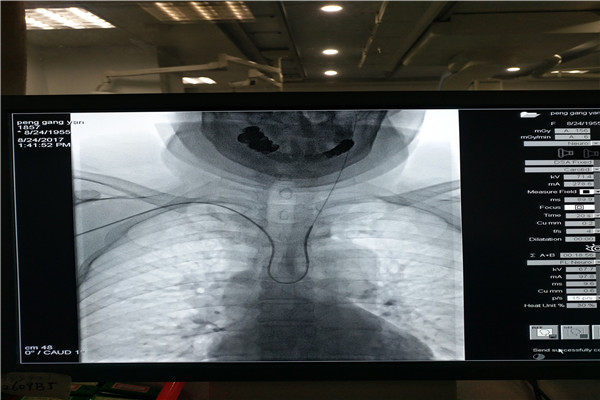

脑血管疾病因其发病率高、致残致死率高、复发率高等特点已经成为人民群众特别是老年人群的重要健康杀手。全脑血管造影是脑血管病诊断的金标准。传统全脑血管造影术(DSA术)主要经股动脉穿刺进行,虽然效果良好,但具有卧床时间长等缺点,为了让群众享受到更加方便快捷的诊疗服务,近日,我院神经内科二病区潘鹏克主任率领医疗团队凭借多年经股动脉穿刺途径行脑血管造影的经验,顺利完成经桡动脉入路进行全脑血管造影术,取得满意效果。

经桡动脉穿刺脑血管造影术是目前国内最先进的脑血管造影方式,与传统经股动脉穿刺脑血管造影相比,经桡动脉穿刺脑血管造影术具有手术创伤小、出血少、痛苦少、术后恢复快、安全性高、无需长时间卧床观察等优点,该项技术的开展将为河池脑血管疾病患者带来福音。